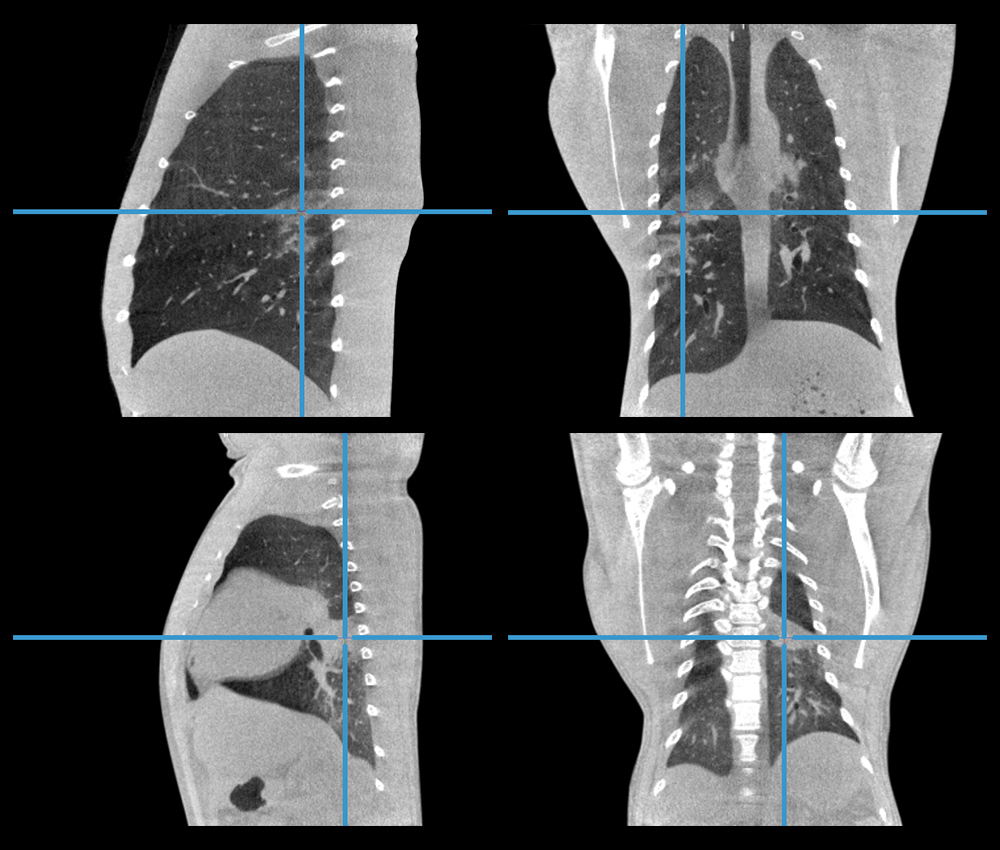

使用CT对SARS-CoV-2感染进行成像

CT系统的高空间分辨率且各向同性非常适合表征肺部病变。

〉动物:M. Fascicularis(5公斤/11磅)

〉采集:屏气CT

〉总扫描时间:36秒

高分辨率肺部成像

在结核病研究中,会利用肺部高分辨率成像技术。采用屏气CT扫描方案或呼吸门控技术有助于显示肺部肉芽肿。